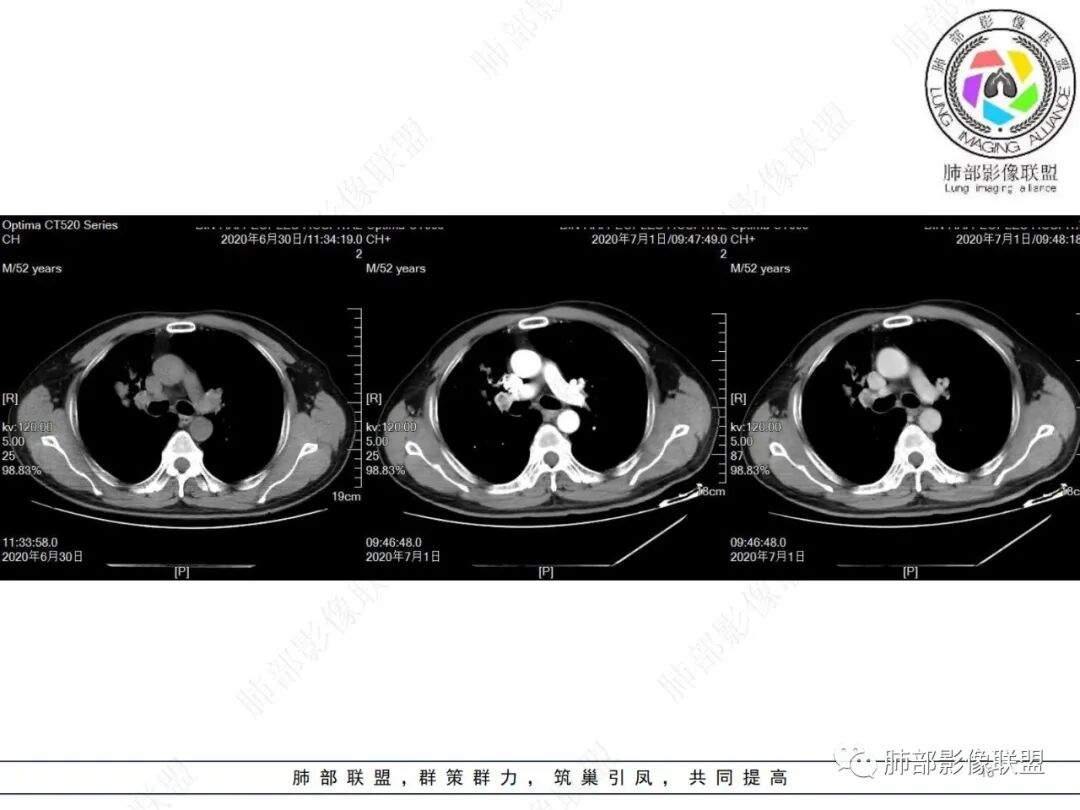

不符合鳞癌有四点:1,截断的支气管不在肿块中央,而是外朝内爬行(肿块外缘大于近端)2、支气管截断在前段,前段远端没有阻塞性改变。3、鳞癌是近端强化,远端为阻塞性的不强化粘液栓或明显强化的不张肺组织,这个是中间坏死,周围强化的肿瘤组织。4、肿瘤标志物CEA增高太明显,鳞癌标志物不高。

1. 鳞癌的坏死

肺鳞癌的坏死,比较彻底;坏死区分布,呈湖泊样;坏死区边界清,有较多壁结节;周围型鳞癌的坏死,边界凹凸不平,因为坏死逐渐融合;鳞癌的强化,非坏死区与坏死区强化幅度差距大。

2..肺腺癌的坏死

没到低分化程度,基本不会出现坏死;腺癌的坏死常不彻底,坏死可以很大一块,肿瘤区坏死出现,较模糊,远不如鳞癌坏死显著;空洞偶尔可见,空洞边缘似乎有特点;低分化腺癌,常伴纵隔淋巴结肿大。